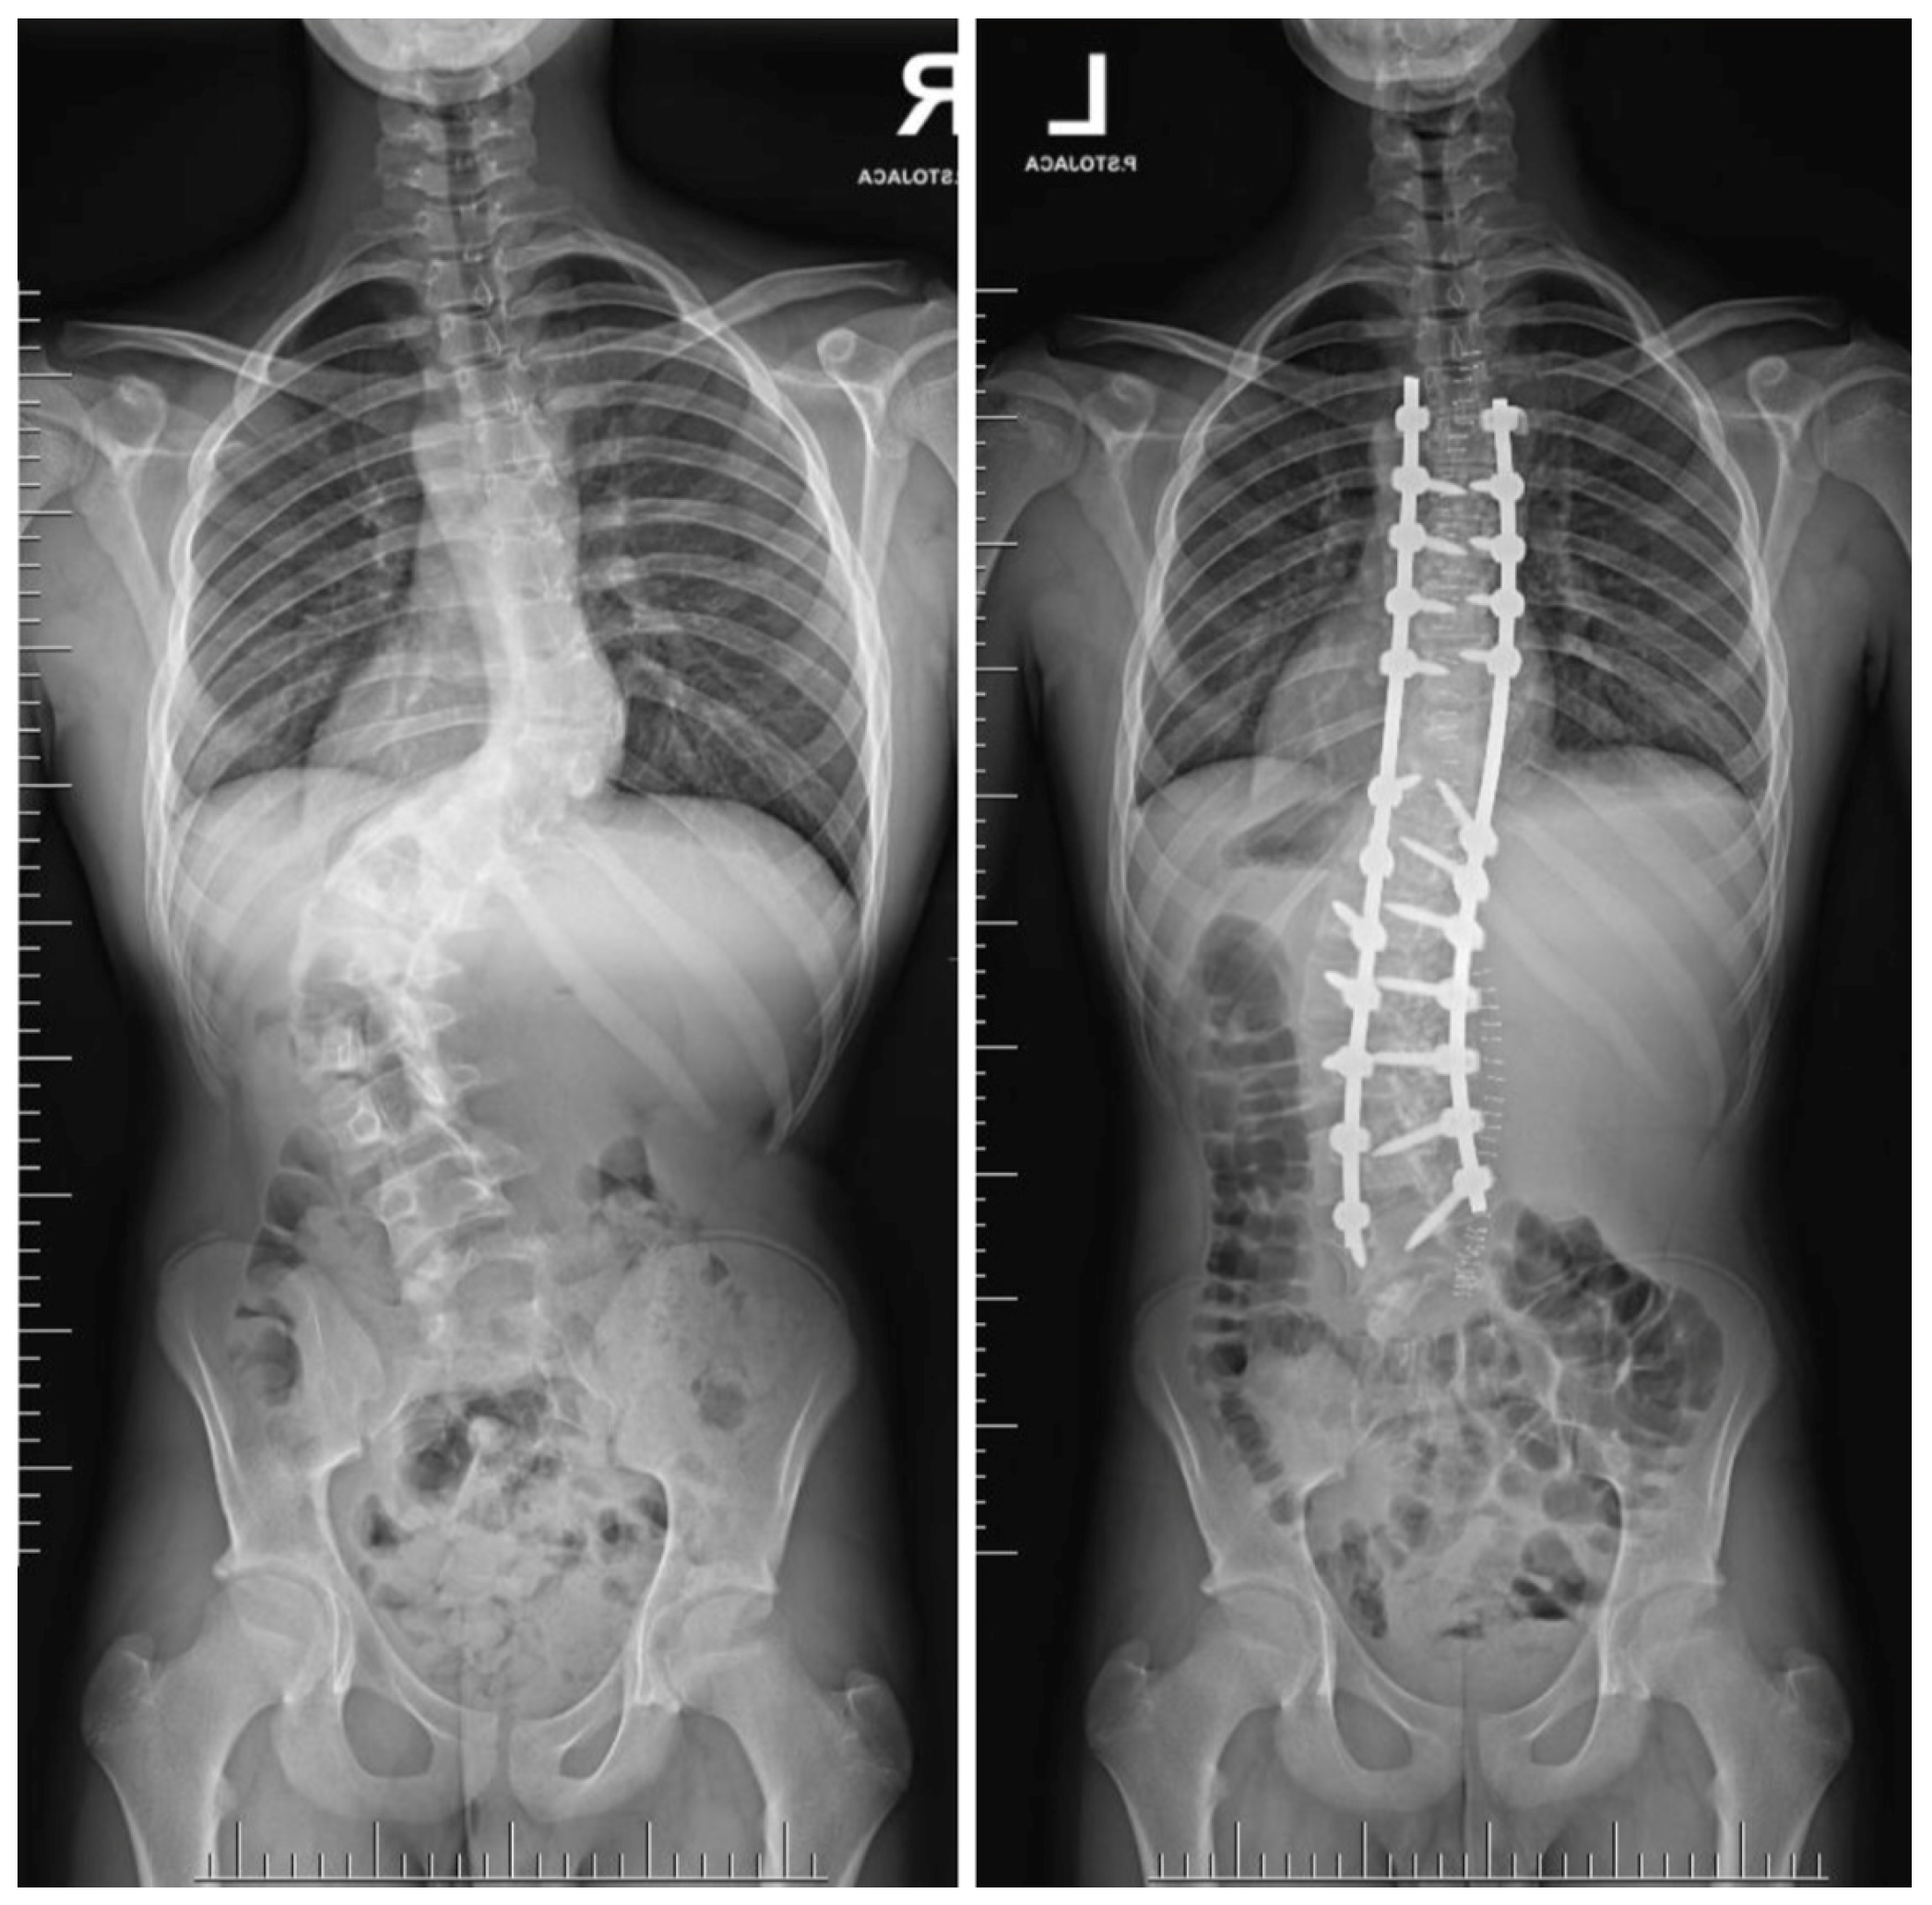

- Suk, S.I.; Chung, E.R.; Kim, J.H.; Kim, S.S.; Lee, J.S.; Choi, W.K. Posterior vertebral column resection for severe rigid scoliosis. Spine 2005, 30, 1682–1687. [Google Scholar] [CrossRef] [PubMed]

- Suk, S.I.; Kim, J.H.; Kim, W.J.; Lee, S.M.; Chung, E.R.; Nah, K.H. Posterior vertebral column resection for severe spinal deformities. Spine 2002, 27, 2374–2382. [Google Scholar] [CrossRef] [PubMed]

- Grabala, P.; Fani, N.; Gregorczyk, J.; Grabala, M. Posterior-only T11 vertebral column resection for pediatric congenital kyphosis surgical correction. Medicina 2024, 60, 897. [Google Scholar] [CrossRef] [PubMed]

- Asunis, E.; Cini, C.; Martikos, K.; Vommaro, F.; Evangelisti, G.; Griffoni, C.; Gasbarrini, A. Efficacy and Risks of Posterior Vertebral Column Resection in the Treatment of Severe Pediatric Spinal Deformities: A Case Series. J. Clin. Med. 2025, 14, 374. [Google Scholar] [CrossRef]

- Song, Z.; Zhang, Z.; Yang, X.; Zhao, Z.; Li, T.; Bi, N.; Xie, J.; Wang, Y. Posterior Vertebral Column Resection for Severe Spinal Deformity Correction: Comparison of Pediatric, Adolescent, and Adult Groups. Comput. Intell. Neurosci. 2022, 2022, 5730856. [Google Scholar] [CrossRef]

- Karami, M.; Zandi, R.; Hassani, M.; Elsebaie, H.B. Thoracolumbar and Lumbar Posterior Vertebral Resection for the Treatment of Rigid Congenital Spinal Deformities in Pediatric Patients: A Long-Term Follow-up Study. World Neurosurg. X 2022, 16, 100130. [Google Scholar] [CrossRef]